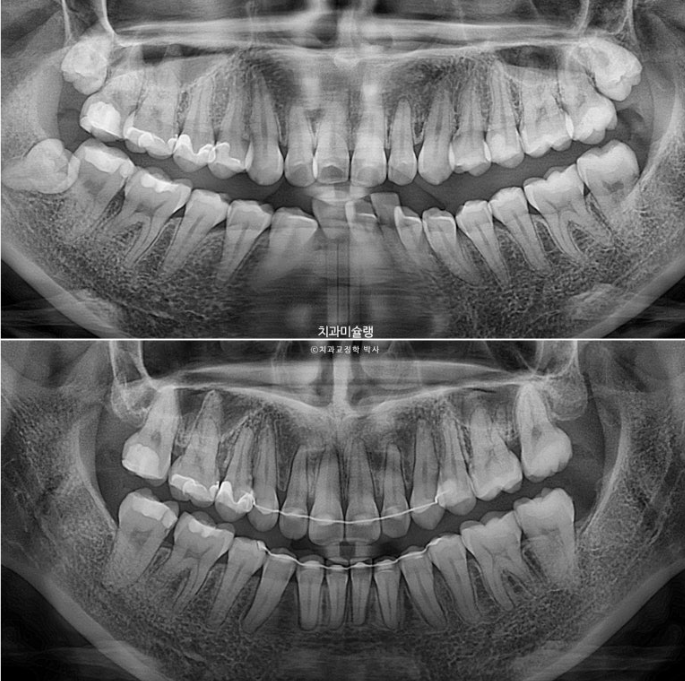

파노라마 엑스레이에서 치근평행도는 좋고 치근흡수도 관찰되지 않습니다.

오히려 뻗쳐있던 앞니가 정상각도를 찾으면 이 경우처럼 파노라마 엑스레이상 치아뿌리가 더 길어보입니다.